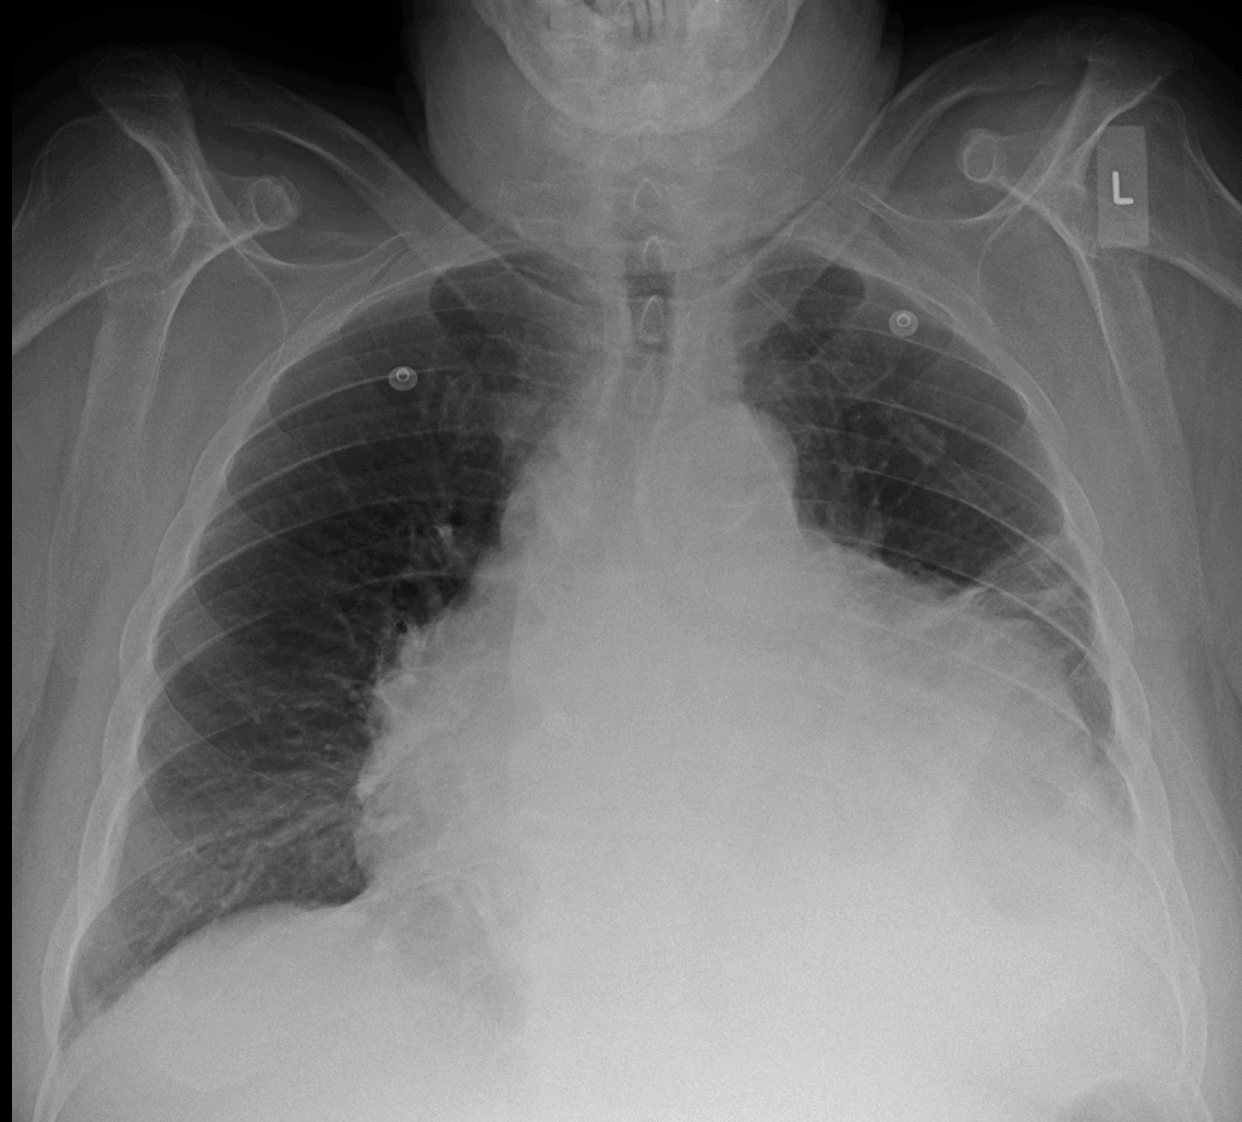

Cardiac Tamponade Chest X Ray Tampon On X Ray The differential diagnosis is a rectal foreign body. The examination includes a genital exam, which may include a pelvic exam with a speculum. The purpose of a tampon is to absorb blood during menstruation, and so after. Imaging is an option if the diagnosis is unclear or complications are suspected;. Tampons (sanitary wear for females) are made of a blend. Tampon On X Ray.

Cardiac Tamponade Chest X Ray Tampon On X Ray Therapeutic foreign bodies include tampon, menstrual cup, vaginal mesh, and a variety of pessaries that are used for support in. In this case, a tampon is present here as an incidental finding. The differential diagnosis is a rectal foreign body. The examination includes a genital exam, which may include a pelvic exam with a speculum. Tampons (sanitary wear for females). Tampon On X Ray.